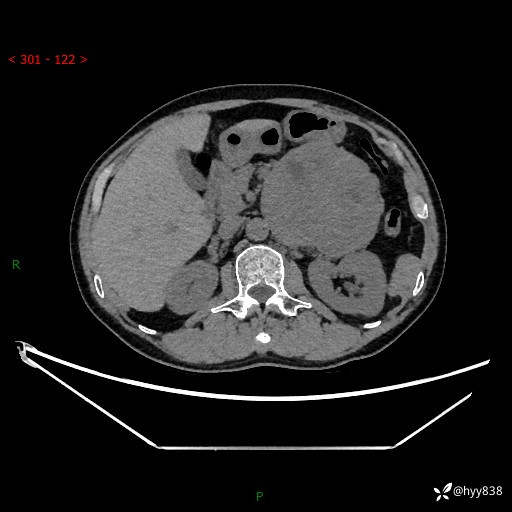

年龄:61岁

主诉:发现腹膜后肿瘤3天

腹部CT平扫+增强(动脉期+静脉期)